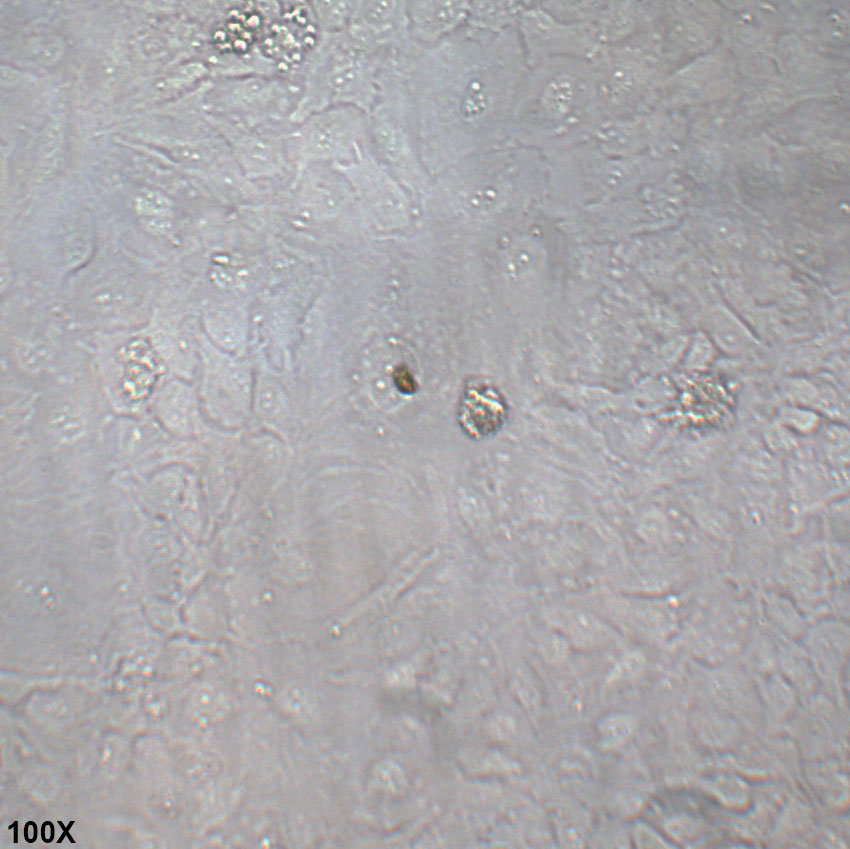

形态特征 上皮细胞样

生长特征 贴壁